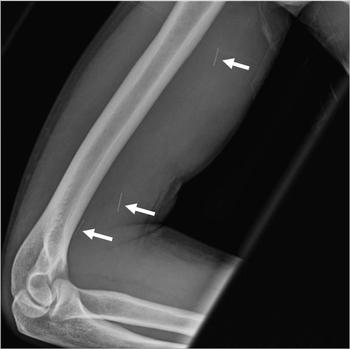

X-rays show that patients with osteoarthritis who receive a hip steroid/anesthetic injection may develop osteonecrosis of the hip.